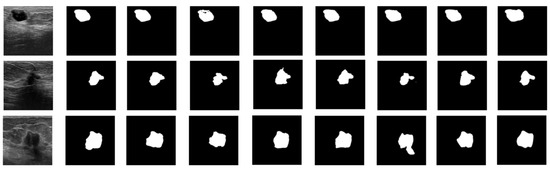

4.1. Dataset and Preprocessing